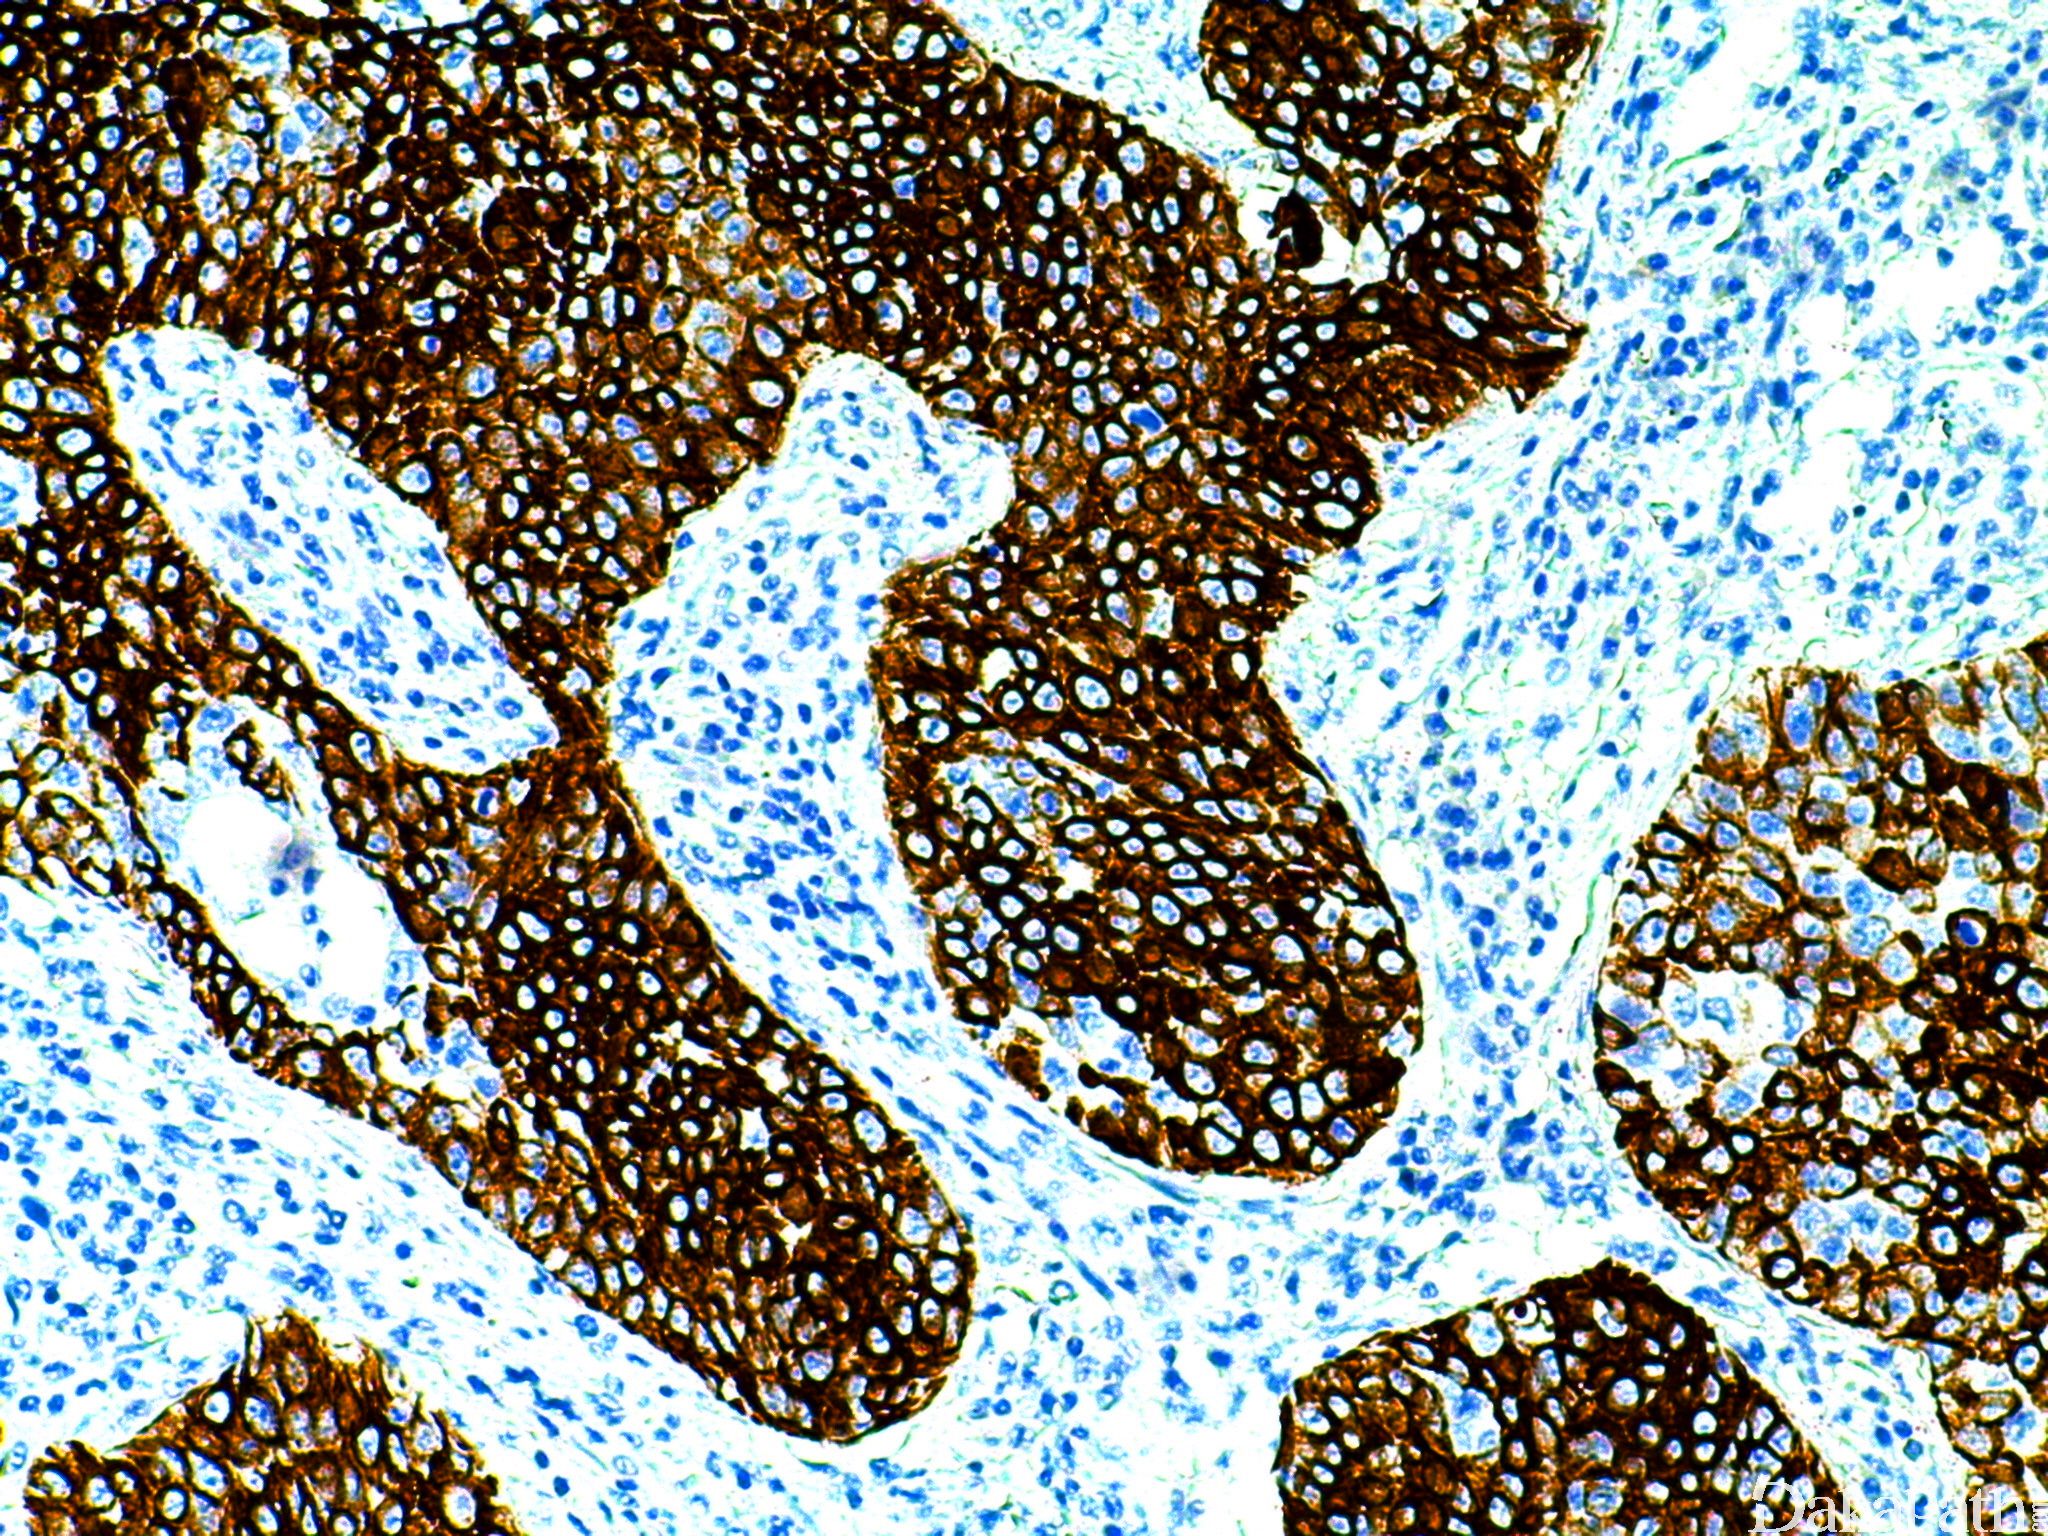

CK5/6

CK5 分子量为 58kDa,与 CD14 协同作用,和 CK6 关系密切(抗体常同时与 CK5、CK6 反应)。鳞状上皮及导管上皮的基底细胞和部分鳞状上皮生发层细胞、间皮细胞阳性,腺上皮细胞阴性。胸腺瘤中的上皮样成分阳性。基底细胞样乳腺癌的确诊标记物之一。也用于乳腺 UDH 与导管上皮异性增 生(ADH、DCIS、ALH、LCIS 等)的鉴别。

信号定位: 胞质

乳腺导管增生(强阳)与实性乳头状癌(阴性);